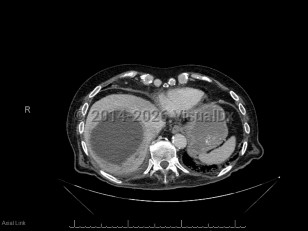

Abdominal aortic aneurysmAbdominal aortic aneurysm